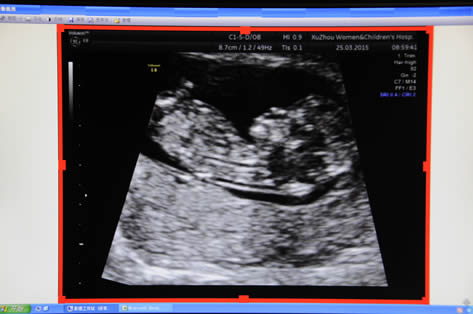

NT超聲成像

產科:早孕(yùn)期NT、普通產科、係統(tǒng)超聲(四維)、針對性產前超聲、單項產科等;